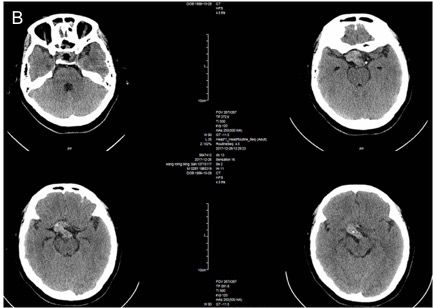

术后第三天复查鞍区CT及MRI,可见鞍内填塞物,未见出血或颅内积气等脑脊液漏等征象(图5)。

图5. A术后垂体增强MRI;B术后鞍区CT